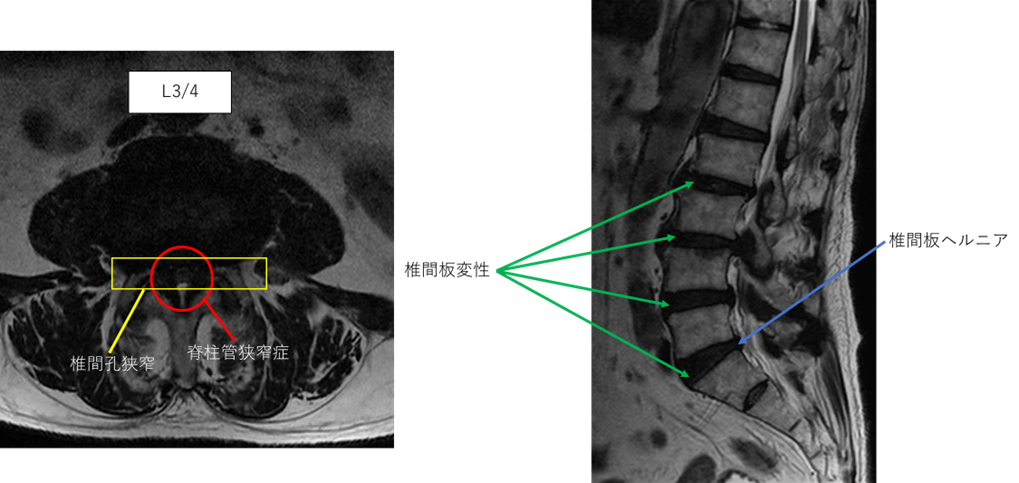

L1/2: 異常なし

L2/3: 椎間板変性症、右椎間孔狭窄

L3/4: 椎間板変性症、脊柱管狭窄症、両椎間孔狭窄

L4/5: 椎間板変性症、左椎間孔狭窄

L5/S: 椎間板変性症、椎間板ヘルニア、右椎間孔狭窄

以上の事が画像上認められます。